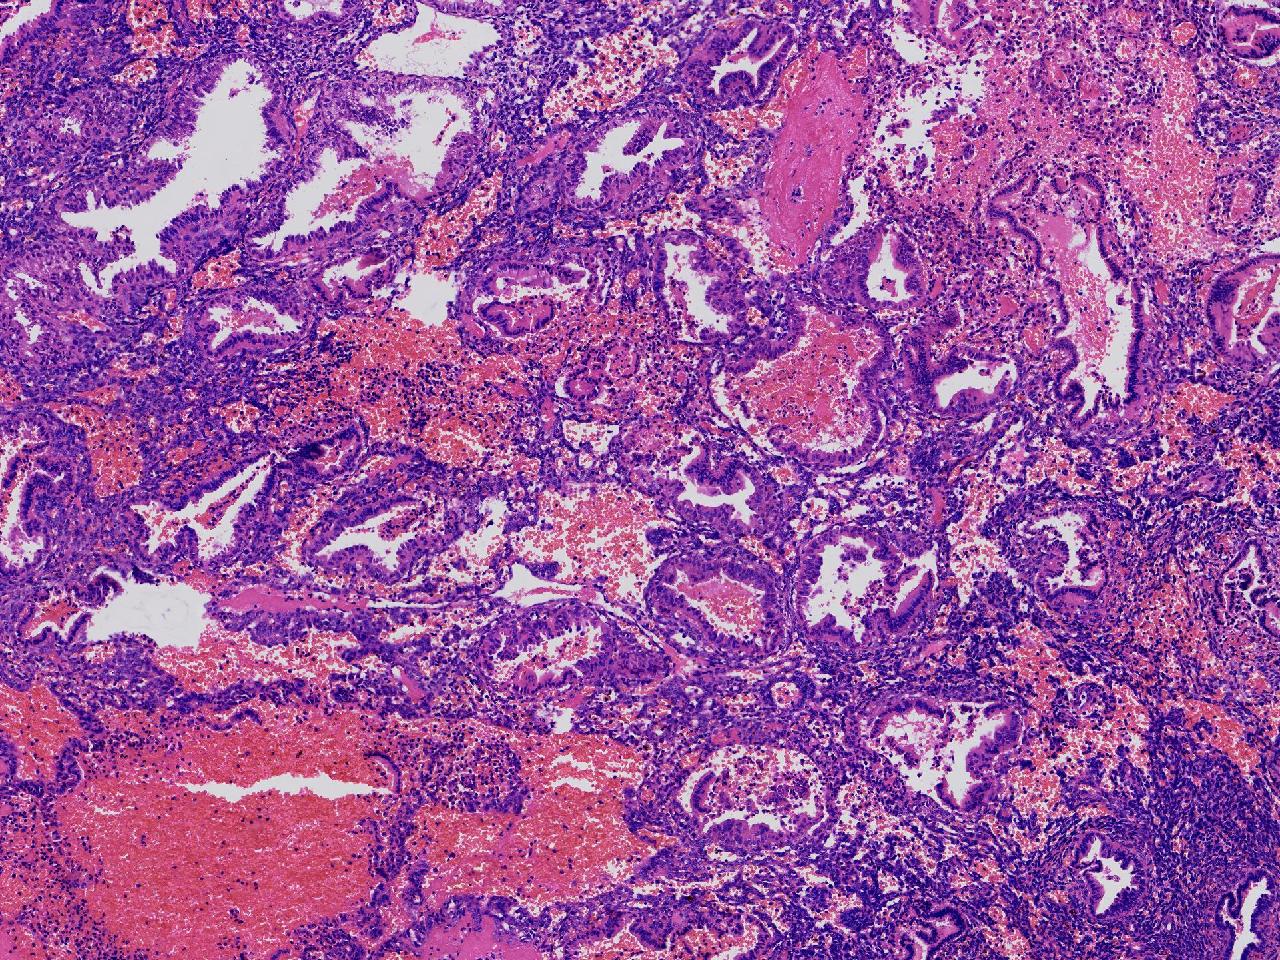

性别

女

年龄

45岁

临床诊断

阴道不规则出血20余天,

一般病史

彩超示:宫腔内见约41X11毫米的不均质回声区。宫腔镜示:宫腔形态正常,内膜粉红,不规则增厚。

标本名称

子宫内膜

大体所见

灰粉色不整形软组织多块,1.5X1X0.6厘米。

分泌反应子宫内膜,伴有出血。

晚泌期及月经早期改变,局部呈啫酸性乳头状化生改变。